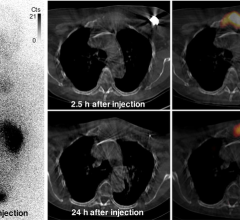

April 3, 2023 — NorthStar Medical Radioisotopes, LLC, a global innovator in the development, production and ...